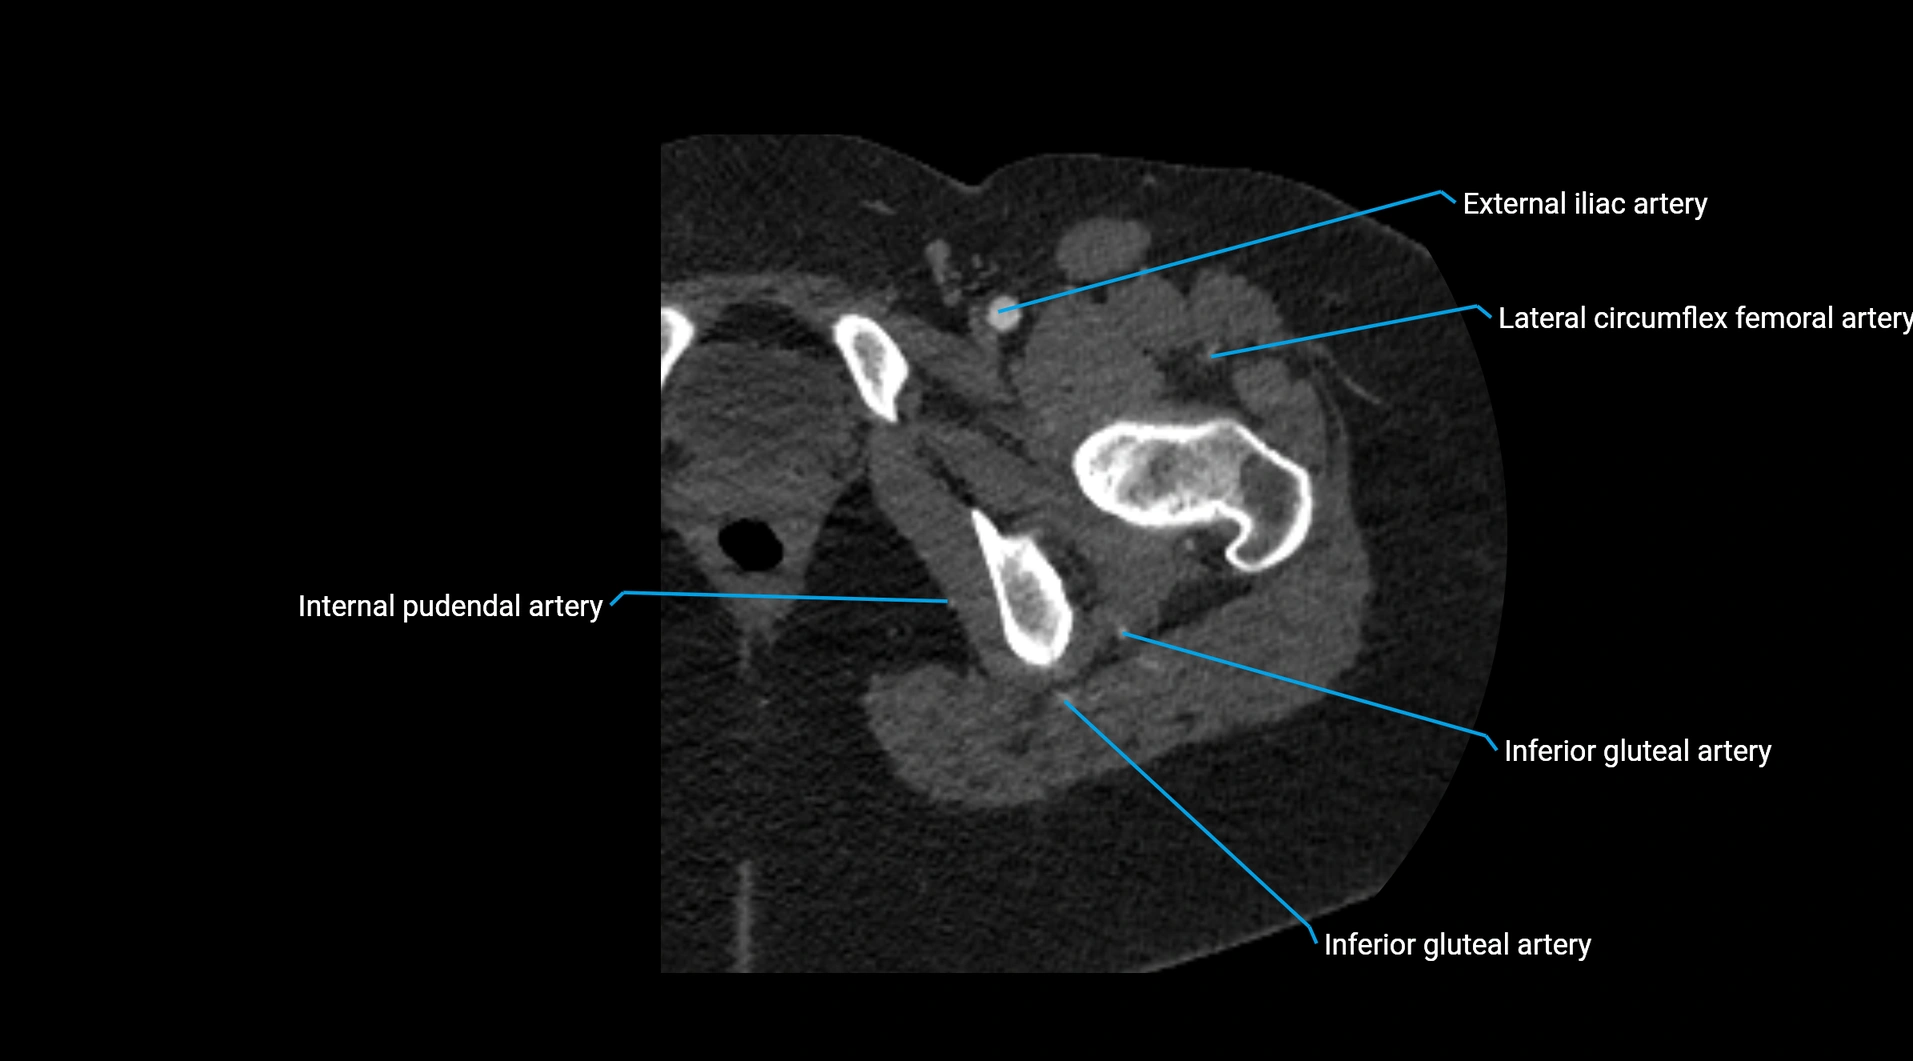

CT images

image

Contrast-enhanced CT (CTA):

• Gold standard for abdominal aortic imaging

• Provides excellent detail of lumen, wall, aneurysm, thrombus, and branch vessels

• Multiplanar and 3D reconstructions help in aneurysm measurement, stent graft planning, and dissection evaluation